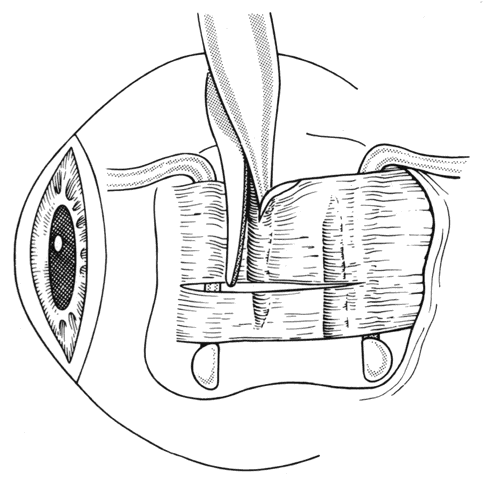

If a rectus muscle has been recessed 5 mm or more, further recession will put the new insertion at or beyond the arc of contact of the rectus muscle and the globe. This may cause decreased function of the muscle and produce noncomitant ocular rotations, especially in extreme gaze positions. To weaken a rectus muscle without disturbing its insertion site, a marginal myotomy can be performed.39,40 Usually, two separate cuts are made into the muscle near the tendon (Fig. 36) until the muscle lengthens. The weakening effect can be graded by increasing the number of cuts from two to three or by increasing the percent of the muscle that is cut. To be effective, a marginal myotomy should be accompanied by resection of the ipsilateral antagonist muscle.

Fig. 36. To perform a marginal myotomy, the muscle tendon is gently stretched between two Jameson muscle hooks. Prophylactic hemostasis is achieved by clamping the muscle or by application of a wet-field cautery to blanch the vessels in the tendon. The muscle is cut with small “snips” using a Wescott scissors.

If a muscle tendon has been split during mobilization of the tendon or by passing a muscle hook under a scarred tendon, the marginal myotomy should be avoided. Placing cuts in the muscle may cause the muscle to be transsected (Figs. 37 through 40).